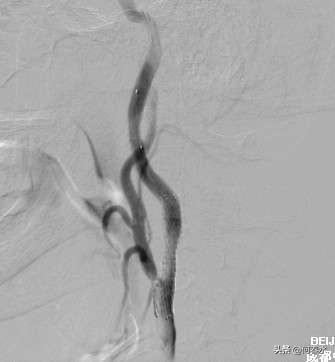

影像资料如下:

图片说明:支架植入后,狭窄完全消失,远端保护伞随后取出